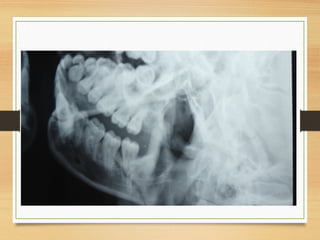

Diagnostic imaging

• Plain radiograph still provides the foundation of imaging

• To adequately screen for the presence of a mandibular

fracture, at least two views at right angles to each other are

necessary

• The mandibular views include

• Intraoral periapical view: to determine the involvement of the teeth.

Could be used to assess soft tissue impaction of tooth segment

• Occlusal view: to assess the symphyseal and parasymphyseal region

due to distortion seen on postero-anterior view

Occlusal view

Diagnostic imaging cont

• Orthopanthomogram

 Extraoral views

 Postero-anterior projection shows mediolateral

displacement of fracture of the body, angle, ramus

or condylar regions

• Right and left lateral oblique of the mandible: the two sides are taken

for comparison, useful for the body, angle, ramus and condyle

• Rotated PA: the ray is centred away from the cervical spine. Useful for

symphyseal and parasymphyseal with no associated cervical spine

injury